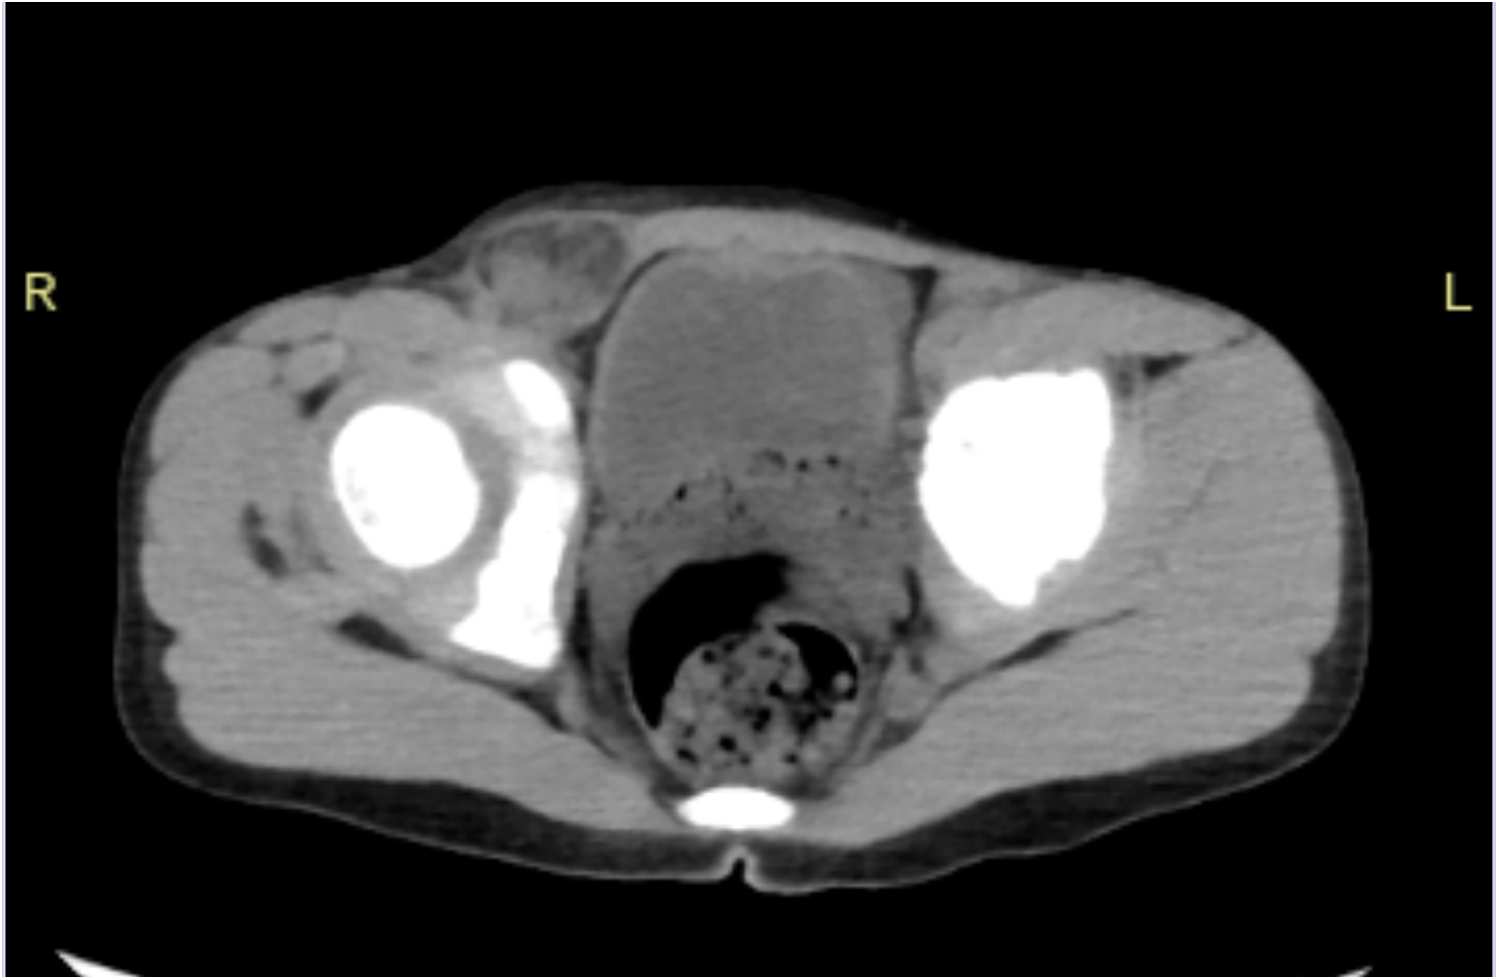

In December 2024, our hospital's emergency department admitted a 6-year-old boy. The patient presented with a painful mass in the right inguinal region that could not be reduced for 8 h. After admission, a physical examination showed that the patient's abdomen was flat and soft, without obvious tenderness, rebound tenderness, or muscle tension. There was deep tenderness in the right inguinal region near the pubic symphysis, without rebound tenderness. A mass of about 3 cm × 3 cm in size was visible in the right inguinal region, with no redness or swelling on the surface, positive for tenderness, and it could not be reduced. An auxiliary examination showed that the blood routine white blood cells were 10.34 × 109/L (reference value: 3.5–9.5 × 109/L) and neutrophils were 7.19 × 109/L (reference value: 1.8–6.3 × 109/L). A lower abdominal CT showed that a part of the small intestine and fat in the right inguinal region herniated into the right hernial sac, and no other abnormalities were found, suggesting right inguinal hernia (Figure 1). The child had a history of surgical treatment for “right inguinal hernia” in our hospital 4 years ago.

Figure 1

CT of the lower abdomen showed a part of the small intestine and fat in the right inguinal region herniated into the right hernial sac.